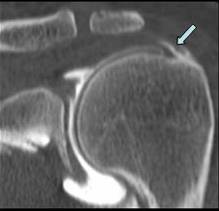

TENDINOPATIE

CALCIFIANTA

A TENDONULUI DIRECT AL MUSCHIULUI DREPT FEMURAL

Insertia tendonului direct al m. drept femural

pe spina Iliaca

antero inferioara →

Tendonul este ingrosat, hipoecogen →

cu mici calcificari →